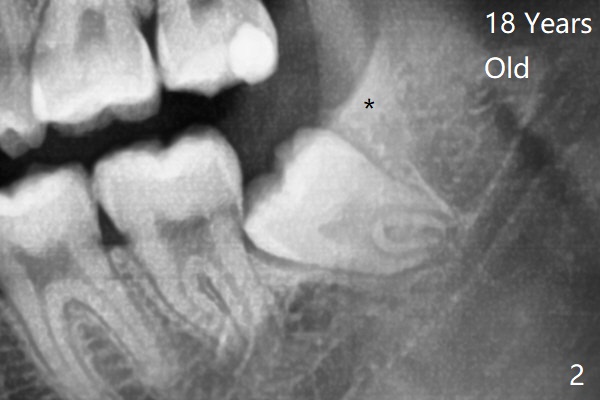

18岁时三角形变大,密度增高(图二)。其实术中发现外斜嵴两侧都不明显(女孩原因?),拔除两侧都需要颊侧去骨。由于左侧智齿颊侧阻生(图三:*),拔除后两侧都放置骨水泥(Bond Apatite,图四:A)促进骨修复,口腔卫生欠缺,可能容易形成牙周炎。